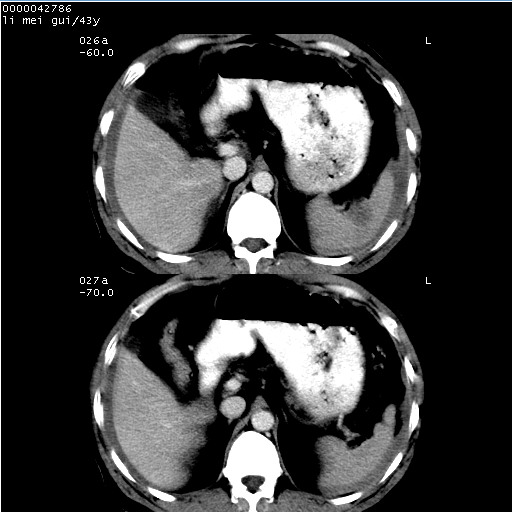

| 患者,男,43岁。突发腹痛2小时,面色苍白,难以平卧。自述近期无明确外伤史,为摩托车驾驶员。 腹部b超检查:脾脏中上极回声异常,肿瘤待排。 临床诊断:腹痛原因待查。 上中腹部ct轴位平扫+增强扫描(层厚10mm,螺距1.0,重建间隔10mm),图像如下: ![]() ![]() ![]() ![]() ![]() ![]() ![]() ![]() ![]() ![]() ![]() ![]() ![]() ![]() ![]() ![]() ![]() ![]() ![]() ![]() ![]() ![]() ![]() ![]() ![]() ![]() ![]() ![]() ![]() ![]() ![]() ![]() ![]() ![]() ![]() zrs发言:支持脾破裂 wwp发言:支持脾破裂并腹水。 xulianj发言:脾脏肿瘤破裂可能性大 zsl6918发言:不像肿瘤出血,考虑还是与外伤后引起的慢性出血有关 zzyy发言:平扫见肝周及脾周积液,脾内密度不均。脾内肿瘤较少见。还是外伤性脾破裂。 沈丘东方医院发言:脾门区一个不均匀强化病灶与其周液体相连多考虑脾占位破裂出血 yixianman001011发言:脾破裂并腹水是可以肯定的,具体原因多以肿瘤性破裂出血,脾脏淋巴瘤可能性大. 结果: 术后,经详细询问患者,其仔细回忆:一月前骑摩托时左侧腰部与别人有“轻微”触碰,因责任在自已,当时又无明显不适,未引起注意。 临床术后诊断:脾破裂并失血性休克(1.外伤性迟发性脾破裂。2.脾脏肿瘤破裂?) 术后标本病检:脾破裂并出血,未见明显肿瘤成份。 原贴地址:http://www.radinet.com.cn/forum_view.asp?forum_id=4&view_id=34070 |